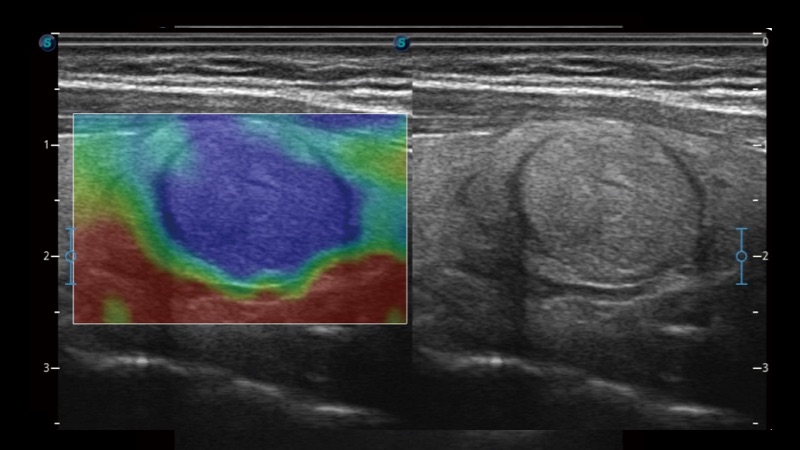

凭借狗万官方网站先进的成像技术和优异的探头技术提供的清晰的图像表现,您可以更自信地做出临床决策。